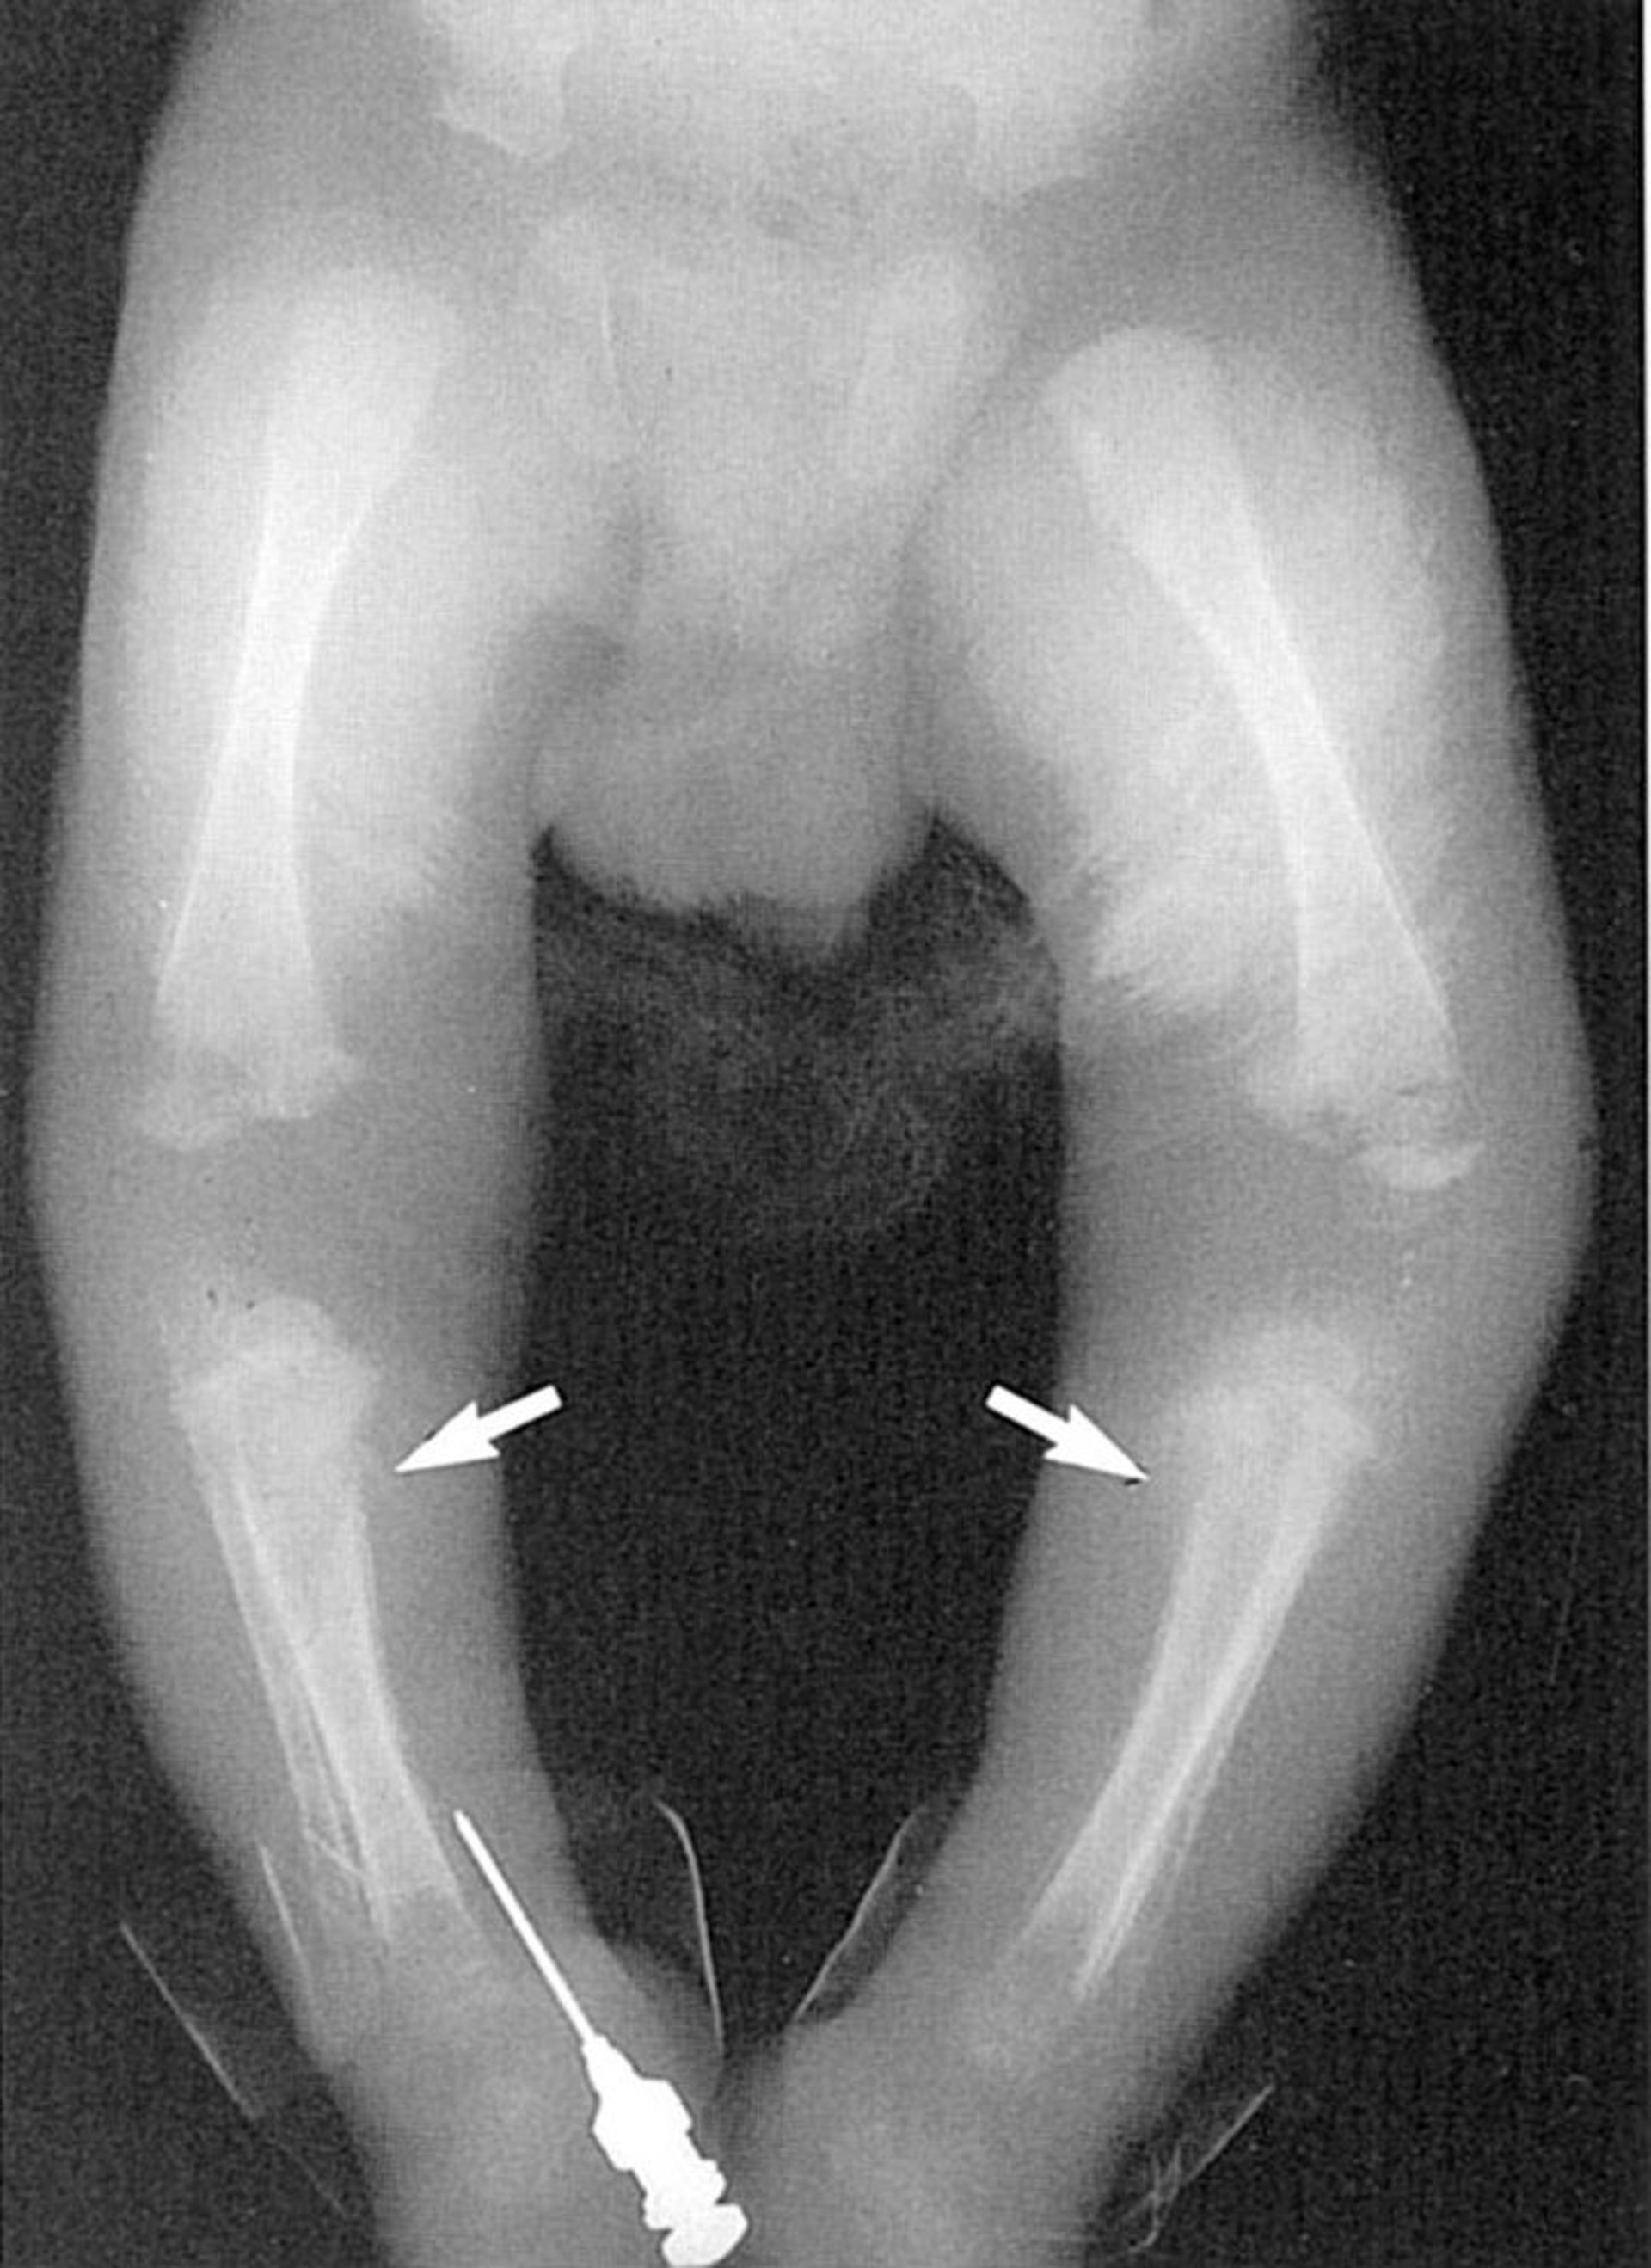

Signo de Wimberger

Esta fotografía muestra lesiones líticas en la tibia proximal medial (flechas).